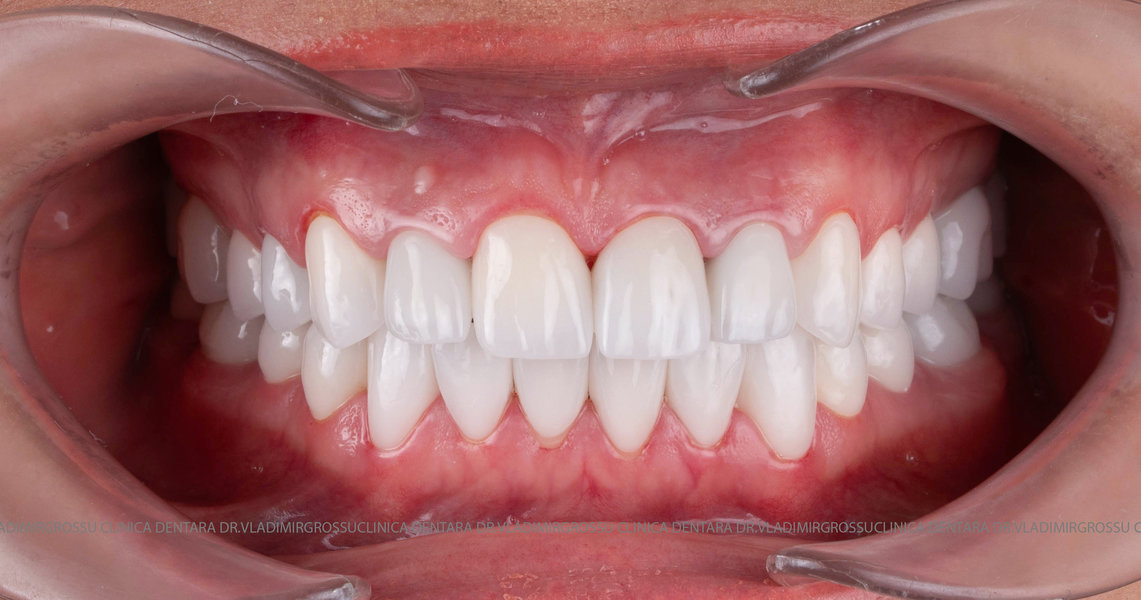

Caz 2

Transformările estetice și impactul reabilitării asupra vieții pacienților

Reabilitarea dentară produce o schimbare vizibilă și profundă în aspectul pacientului, cu efecte pozitive evidente asupra stimei de sine și a calității vieții. Mulți pacienți relatează bucuria redobândirii funcției masticatorii și dispariția complexelor legate de aspectul dentar.